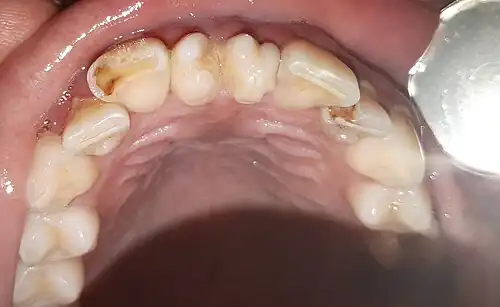

Generalmente presentan una sola raíz, tienen un tamaño muy pequeño y a veces presentan aplasia de los lóbulos mesiales y distales con forma de cono (conoidismo), aunque muchas veces los cuartos molares pueden tener una morfología normal.[5]